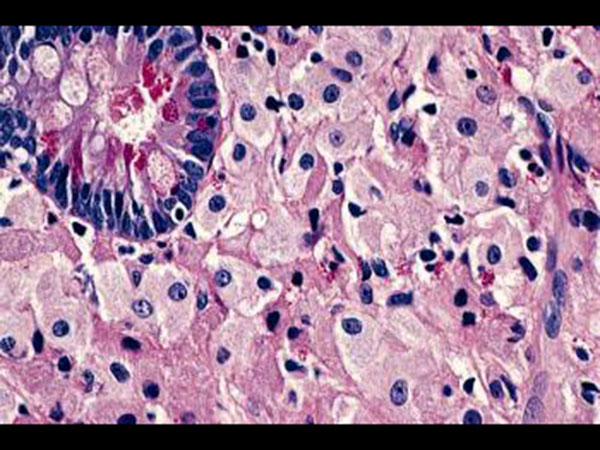

பயாப்ஸி

சிறுகுடலின் சுவரிலிருந்து சிறுதளவு திசுக்களை எடுத்து பரிசோதனை செய்கின்றனர். இந்த திசுக்களை மைக்ரோஸ்கோப் வழியாக ஆய்வு செய்து பாக்டீரியா தாக்கம் இருக்கிறதா, கட்டிகள் இருக்கிறதா என்பதை பார்க்கிறார்கள்.